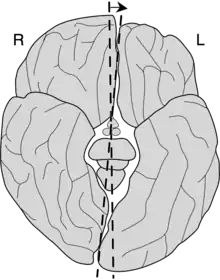

Yakovlevian torque (also known as occipital bending (OB)[1] or counterclockwise brain torque[2]) is the tendency of the right side of the human brain to be warped slightly forward relative to the left and the left side of the human brain to be warped slightly backward relative to the right. This is responsible for certain asymmetries, such as how the lateral sulcus of the human brain is often longer and less curved on the left side of the brain relative to the right. Stated in another way, Yakovlevian torque can be defined by the existence of right-frontal and left-occipital petalias, which are protrusions of the surface of one hemisphere relative to the other. It is named for Paul Ivan Yakovlev (1894–1983), a Russian-American neuroanatomist from Harvard Medical School.[3][4]

A 2012 literature review showed that morphometry studies had consistently found that handedness-related effects corresponded to the extent of the Yakovlevian torque;[5] increased torque, as measured by increased size of the right-frontal petalia and the left-occipital petalia, tends to be more common in right-handed individuals.[6] Individuals with mixed-handedness or left-handedness show reduced levels of Yakovlevian torque.[7]

Reduced right-frontal and left-occipital petalias and reversed petalia asymmetries (that is, left-frontal and right occipital petalias) have been associated with developmental stuttering in both adults and pre-adolescent boys.[2] This may be tied to the lateral sulcus housing Broca's area,[5] which plays a significant role in production of language.

Increased size of the left-occipital petalia, resulting from an abnormally high degree of Yakovlevian torque has been associated with bipolar disorder.[1] Maller et al. 2015 found that increased asymmetry of the occipital lobe, or occipital bending, was four times more prevalent in subjects with bipolar disorder than in healthy controls.[1] This applied both to patients with bipolar disorder type I and type II.

Yakovlevian torque is found in modern humans and fossil hominids, appearing reliably as early as Homo erectus.[6] The patterning of petalias in extinct human ancestors is examined via endocasts, wherein a cast is made of the cranial vault: the asymmetries of human ancestors can be measured from these casts because petalias leave impressions inside the cranial vault.[6]